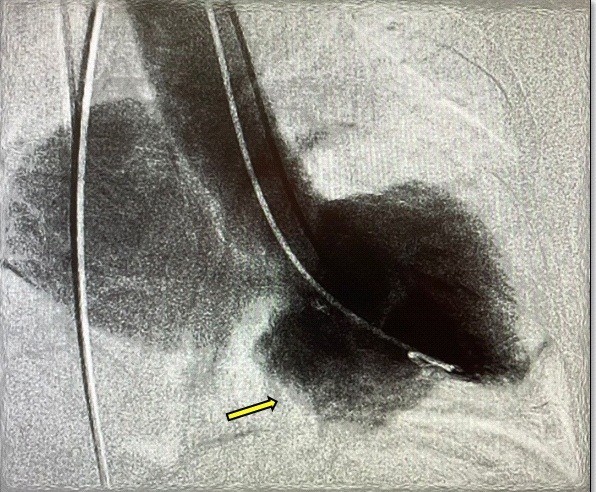

Owing to the suspicion of ischemic etiology (age and risk factors), she underwent diagnostic coronary angiography where epicardial arteries were reported without significant lesions, Markis 4 coronary ectasia, slow pancoronary flow, mitral regurgitation (MR) +++/++++ of Sellers and images suggestive of inferior basal aneurysms, left ventricular ejection fraction (LVEF) of 50%, left ventricular (LV) end-diastolic pressure of 25 mmHg (Fig. 5).

Figure 5. Ventriculogram displays mitral regurgitation of Sellers +++/++++ grade and inferior-basal aneurysm (yellow arrow)